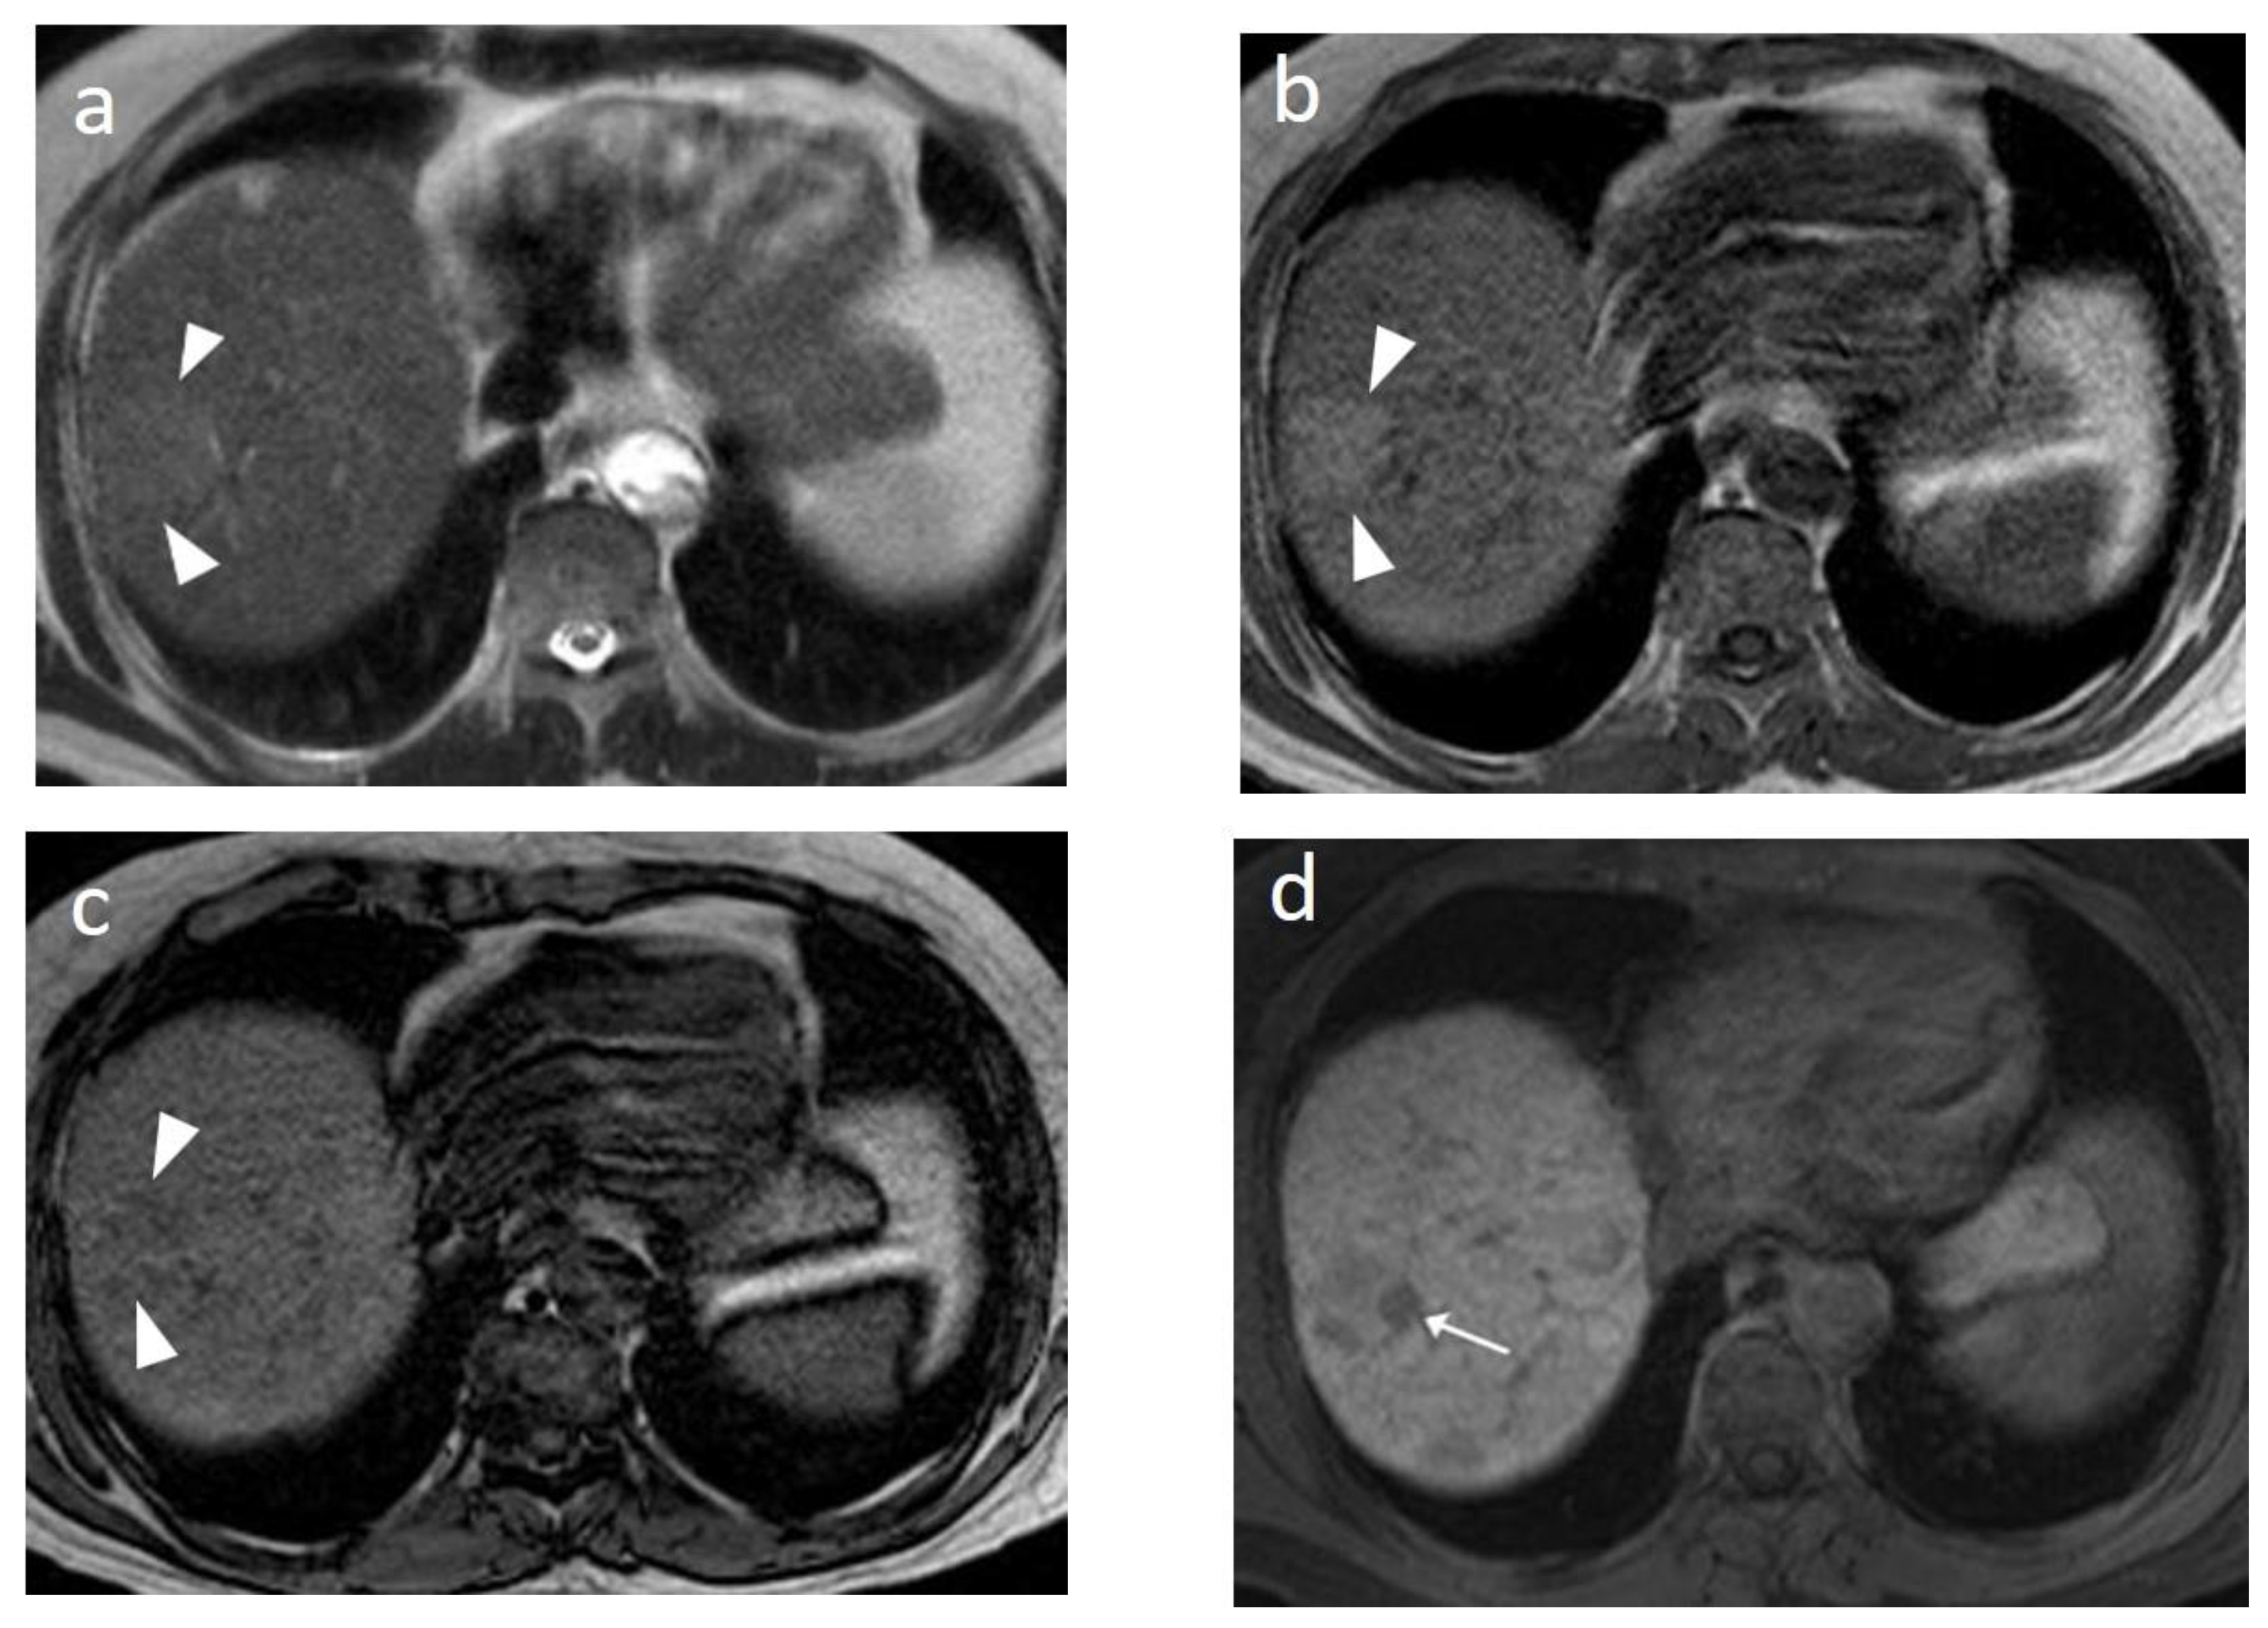

- Kim, Y.K.; Lee, W.J.; Park, M.J.; Kim, S.H.; Rhim, H.; Choi, D. Hypovascular Hypointense Nodules on Hepatobiliary Phase Gadoxetic Acid–enhanced MR Images in Patients with Cirrhosis: Potential of DW Imaging in Predicting Progression to Hypervascular HCC. Radiology 2012, 265, 104–114. [Google Scholar] [CrossRef] [PubMed]

- Park, H.J.; Choi, B.I.; Lee, E.S.; Park, S.B.; Lee, J.B. How to Differentiate Borderline Hepatic Nodules in Hepatocarcinogenesis: Emphasis on Imaging Diagnosis. Liver Cancer 2017, 6, 189–203. [Google Scholar] [CrossRef] [PubMed]

- Shinmura, R.; Matsui, O.; Kobayashi, S.; Terayama, N.; Sanada, J.; Ueda, K.; Gabata, T.; Kadoya, M.; Miyayama, S. Cirrhotic Nodules: Association between MR Imaging Signal Intensity and Intranodular Blood Supply. Radiology 2005, 237, 512–519. [Google Scholar] [CrossRef]

- Park, M.J.; Kim, Y.K.; Lee, M.W.; Lee, W.J.; Kim, Y.-S.; Kim, S.H.; Choi, D.; Rhim, H. Small Hepatocellular Carcinomas: Improved Sensitivity by Combining Gadoxetic Acid–enhanced and Diffusion-weighted MR Imaging Patterns. Radiology 2012, 264, 761–770. [Google Scholar] [CrossRef]